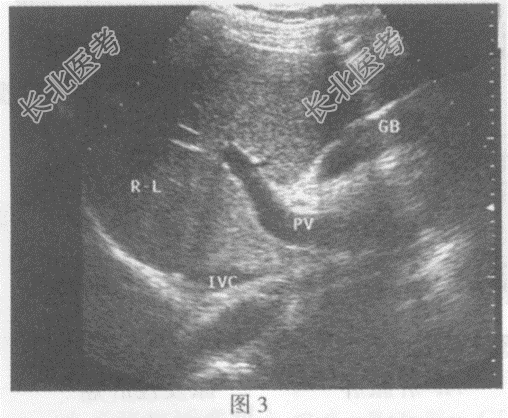

- 单项选择题临床资料:女, 34岁,右位心。

超声综合描述: 右上腹可见脾脏(图1),左上腹可见肝脏(图2), 腹主动脉位于脊柱右前方,下腔静脉位于脊柱左前方(彩图), 胆囊位于左上腹(图3),各脏器形态大小回声未见异常。